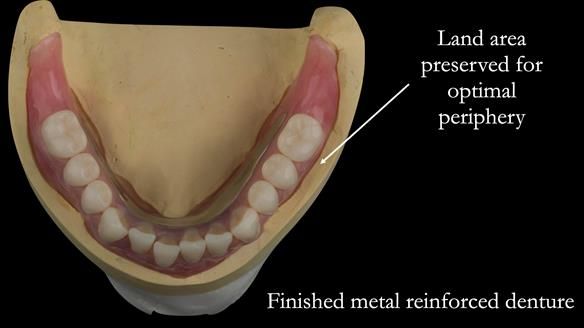

This newsletter describes in step by step detail the provision of a lower implant supported metal based complete denture with three dental implants positioned in the anterior mandible. The upper arch was restored with a metal based complete upper denture.

I provided new metal based complete dentures. The clinical situation and treatment process is shown in detail below with photographs. I provided the clinical work and Rowan Garstang provided the technical work. The dentures took 5 visits to make - with the patient travelling by plane from Ireland to Manchester. The patient had one review after the dentures were fitting.